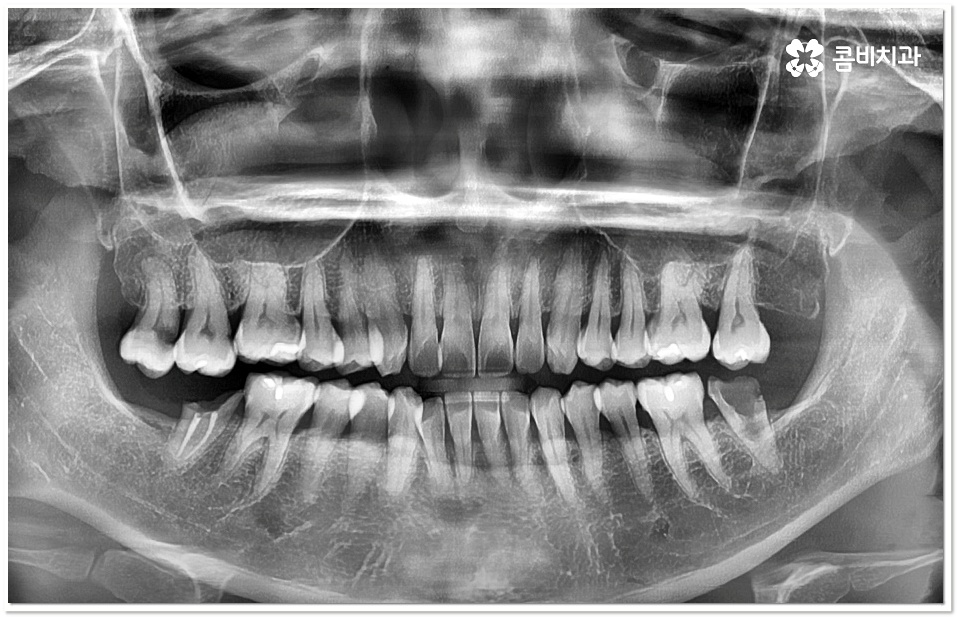

특히 20살 전후로는 사랑니 때문에 인접면 충치가 자주 발생할 수 있으니 신경써 주시길 권유드리고 있는데요. 어금니 뒤쪽으로 사랑니가 나올 때 비정상적으로 맹출이 되어 비스듬한 각도로 어금니와의 사이에 좁은 틈새를 만들게 되면 음식물 찌꺼기가 잘 끼고 쉽게 빠지지 않아 더욱 충치나 잇몸 염증이 유발되기 쉬우니 신경써서 관리해 주시길 바라고 있어요.

이 단계도 지나 치수까지 세균이 침투하게 되면 신경이 변성되고 통증이 심해지기 때문에 신경치료를 통해 이를 제거하고 내부에 충전재를 채워 밀봉한 뒤 전체를 덮어씌우는 크라운 치료를 해 주는데, 이와 같은 보존적 어금니 충치치료 로 자연 치아를 발치하지 않고 내구성을 좀 더 늘릴 수 있습니다.

강도가 중요한 어금니 크라운 재질로 예전에는 금을 많이 사용했었지만 요즘은 자연스러운 심미성을 추구하는 추세라서 치아 색상의 지르코니아를 많이 사용하고 있는데요.

어금니 충치치료 후 신경이 제거된 치아는 추후 2차 감염이 일어나더라도 개인차가 있으나 통증을 느낄 수 없는 경우가 있고, 뿌리쪽에 염증이 생기거나 크라운 안쪽에서 2차 충치가 발생된 경우 육안으로 발견하기도 어렵기 때문에 치료 시기가 더욱 늦어질 수 있어요. 이런 상황에 대비하여 정기적으로 치과에 내원하여 정밀 검진 및 스케일링 처치를 받아주시면 예방과 관리가 한결 용이할 거예요.